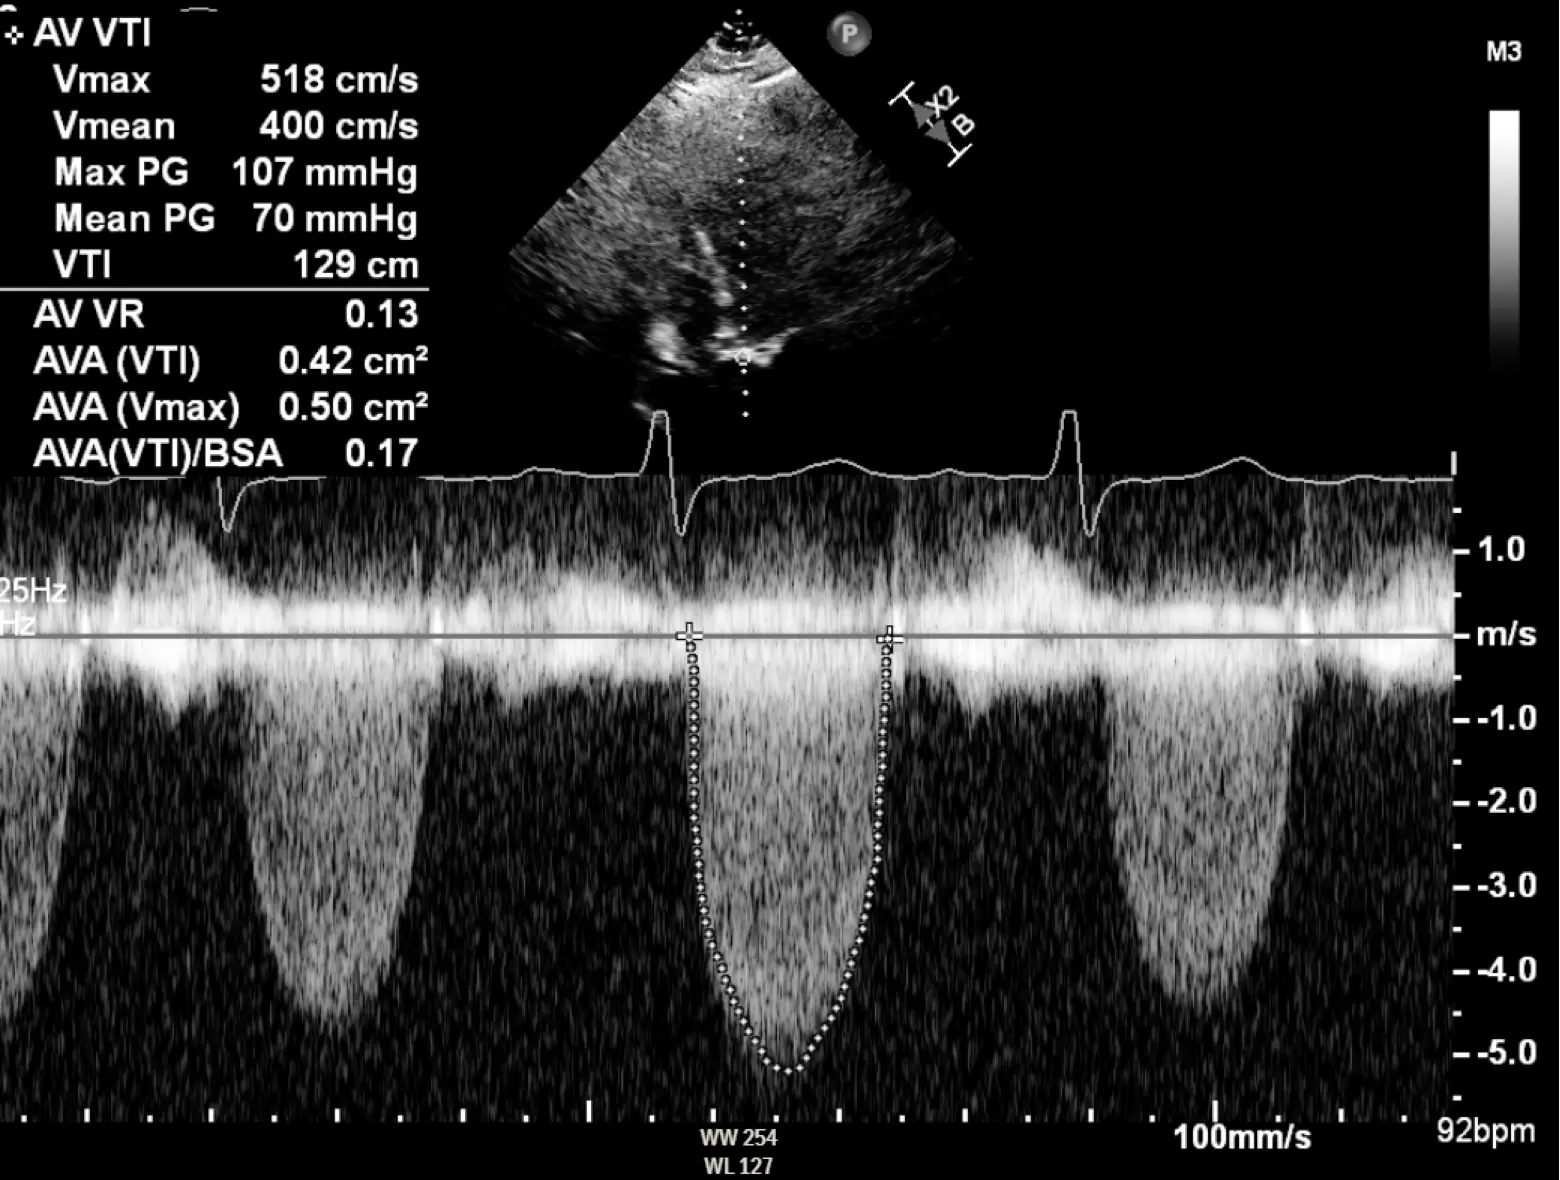

We use the modified Bernoulli equation () to convert the Doppler velocity to pressure gradients across the AV. So as the blood shoots through that tight aortic valve and we clock a velocity of 4 m/s using Doppler on echo, we can convert that to a peak gradient of 64 mmHg, which raises our concern that that poor ventricle is working way too hard.

1, 4, 40, and 64

AVA < 1.0 cm2 Peak velocity > 4 m/s Mean gradient > 40 mmHg Peak gradient > 64 mmHg

- ==Valvular AS will be considered severe if mean gradient > 40 mmHg or peak velocity > 4 m/s (regardless of AVA)==

- Aortic velocity is measured using continuous-wave doppler ultrasound with examination from multiple acoustic windows

- Mean gradient is calculated by averaging instantaneous gradients over the systolic ejection period using the modified Bernoulli equation,

| Aortic sclerosis | Mild AS | Moderate AS | Severe AS | Very Severe AS | |

|---|---|---|---|---|---|

| AVA (cm2) | - | >1.5 | >1.0-1.5 | ≤1.0 | ≤0.60 |

| Mean gradient (mmHg) | - | <20 | 20-40 | >40 | >60 |

| Peak velocity (m/s) | <2.0 m/s | 2.0-2.9 | 3.0-3.9 | ≥4.0 | ≥5.0 |

| Indexed AVA (cm2/m2) | >0.85 | >0.60-0.85 | ≤0.6 | ||

| Velocity ratio | >0.50 | >0.25-0.50 | ≤0.25 |

- The above figure is from the Mayo Echo Boards video where the presenter highlights the importance of calculating the AV TVI in multiple windows to ensure you are appropriately calculating the highest VTI and avoid miscalculation/miscalssification. In Thaden et al (JASE, 2015), the authors found that peak velocity was found outside of the apical window 61% of the time and that neglecting non-apical window misclassified AS 23% of the time.